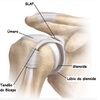

O que é o complexo de GOSS?

Complexo suspensório do ombro >

Escapula

Clavícula

Coracoide

Corpo da glenoide

Ligamentos coraco claviculares

Ligamentos acromio claviculares